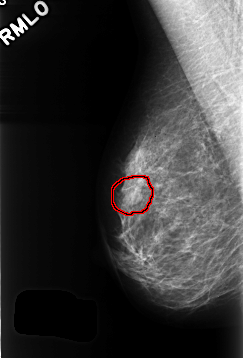

C_0363_1.RIGHT_MLO

RIGHT_MLO LINES 4288 PIXELS_PER_LINE 2912 BITS_PER_PIXEL 12 RESOLUTION 50 OVERLAY

FILE: C_0363_1.RIGHT_MLO.OVERLAY

TOTAL_ABNORMALITIES 1

ABNORMALITY 1

LESION_TYPE MASS SHAPE OVAL MARGINS CIRCUMSCRIBED

ASSESSMENT 3

SUBTLETY 4

PATHOLOGY BENIGN

TOTAL_OUTLINES 1

BOUNDARY